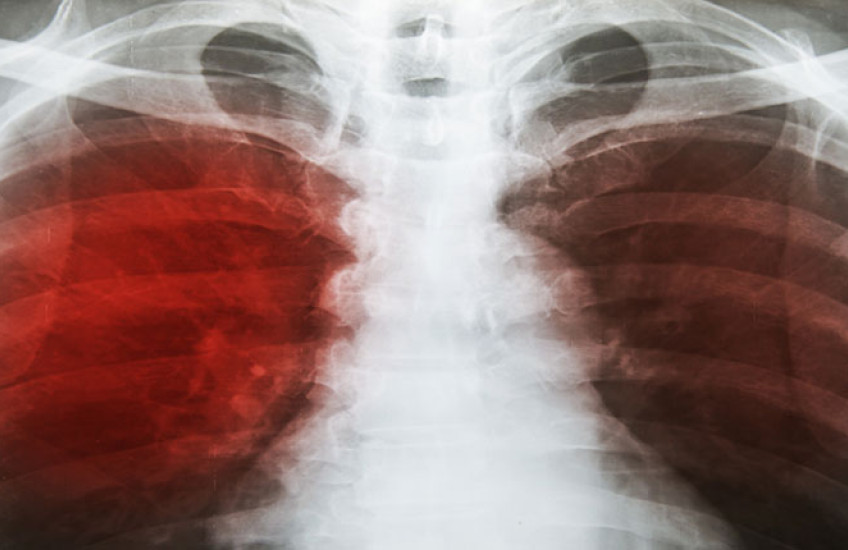

Next, the investigators obtained DNA samples from more than 2,000 people with active TB infections and 2,000 people who lived in the same households who also were infected with TB but had no active disease. To confirm that the apparently disease-free housemates had, indeed, been infected with TB, the researchers screened them using a standard TB skin test, blood tests and X-ray imaging of the lungs to check for the presence of TB in the body. The researchers repeated these tests at two, six and 12 months. This approach allowed the scientists to compare genetic risk among individuals who shared the same environment and had the same or very similar disease exposures.